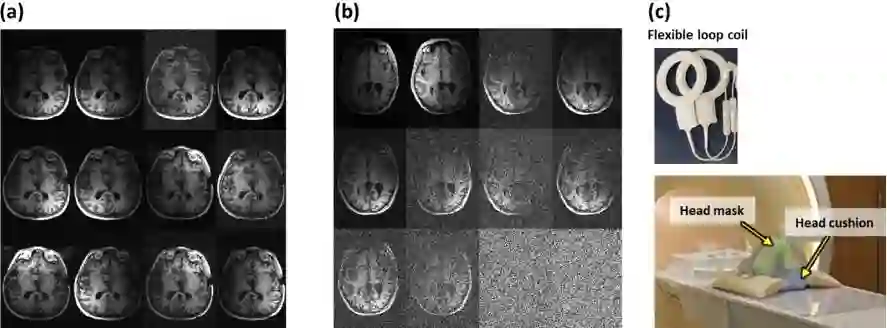

Magnetic Resonance Imaging (MRI) is a non-invasive diagnostic and radiotherapy (RT) planning tool, offering detailed insights into the anatomy of the human body. The extensive scan time is stressful for patients, who must remain motionless in a prolonged imaging procedure that prioritizes reduction of imaging artifacts. This is challenging for pediatric patients who may require measures for managing voluntary motions such as anesthesia. Several computational approaches reduce scan time (fast MRI), by recording fewer measurements and digitally recovering full information via post-acquisition reconstruction. However, most fast MRI approaches were developed for diagnostic imaging, without addressing reconstruction challenges specific to RT planning. In this work, we developed a deep learning-based method (DeepMRIRec) for MRI reconstruction from undersampled data acquired with RT-specific receiver coil arrangements. We evaluated our method against fully sampled data of T1-weighted MR images acquired from 73 children with brain tumors/surgical beds using loop and posterior coils (12 channels), with and without applying virtual compression of coil elements. DeepMRIRec reduced scanning time by a factor of four producing a structural similarity score surpassing the evaluated state-of-the-art method (0.960 vs 0.896), thereby demonstrating its potential for accelerating MRI scanning for RT planning.